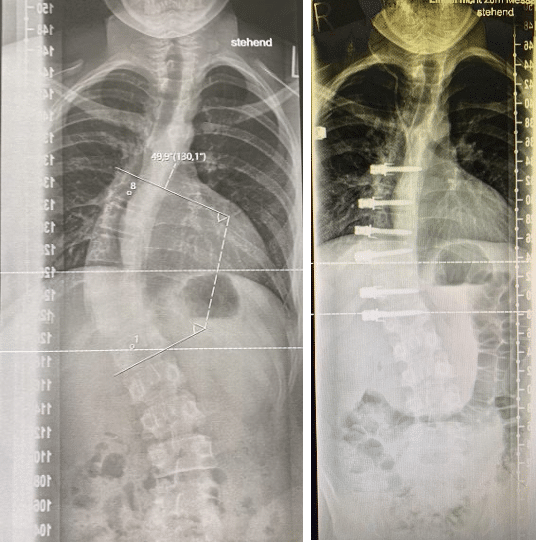

Imágenes de placas de rayos X de una paciente con una escoliosis lumbo-torácica con un ángulo de 50º pre-operatorio (imagen izquierda) comparado con la imagen post-operatoria tras cirugíca ASC /VBT con una curva escoliótica reducida a 20º (imagen derecha). El crecimiento de la paciente reducirá con el tiempo aún más la pequeña curva remanente.